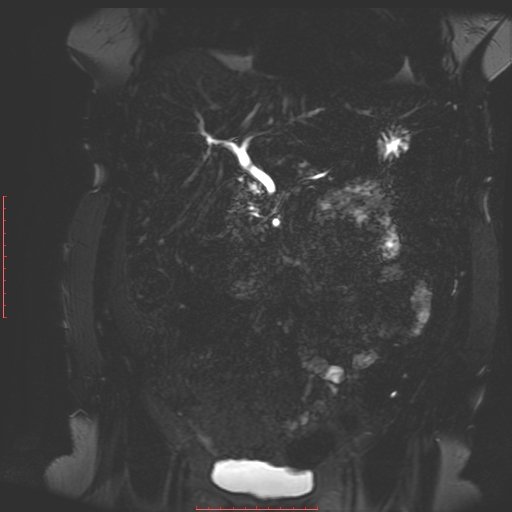

白色文字(排除指定关键词) Imaging Anatomy: interactive PACS-like atlas of radiological anatomy

解剖学模块